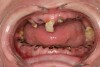

When smoked, methamphetamine produces highly toxic and corrosive fumes of lithium, muriatic, and sulfuric acids that can destroy enamel rapidly. With continued use, methamphetamine can produce severe, rampant caries, similar to early childhood caries. Patients have reported noticing changes in the appearance of tooth structure in as little as 3 months of use. The affected surfaces are the buccal and labial smooth surfaces, as well as the interproximal surfaces (Figure 1 through Figure 3). Because in the general population the vast majority of decay is found in the posterior molars, when someone presents with rampant anterior lesions it should be a red flag for methamphetamine use.5

Figure 1  DEVASTATING EFFECTS When smoked, methamphetamine produces highly toxic and corrosive fumes of lithium, muriatic, and sulfuric acids that can destroy enamel rapidly. With continued use, methamphetamine can produce severe, rampant caries. When someone presents with rampant anterior lesions it should be a red flag for methamphetamine use.

Figure 1